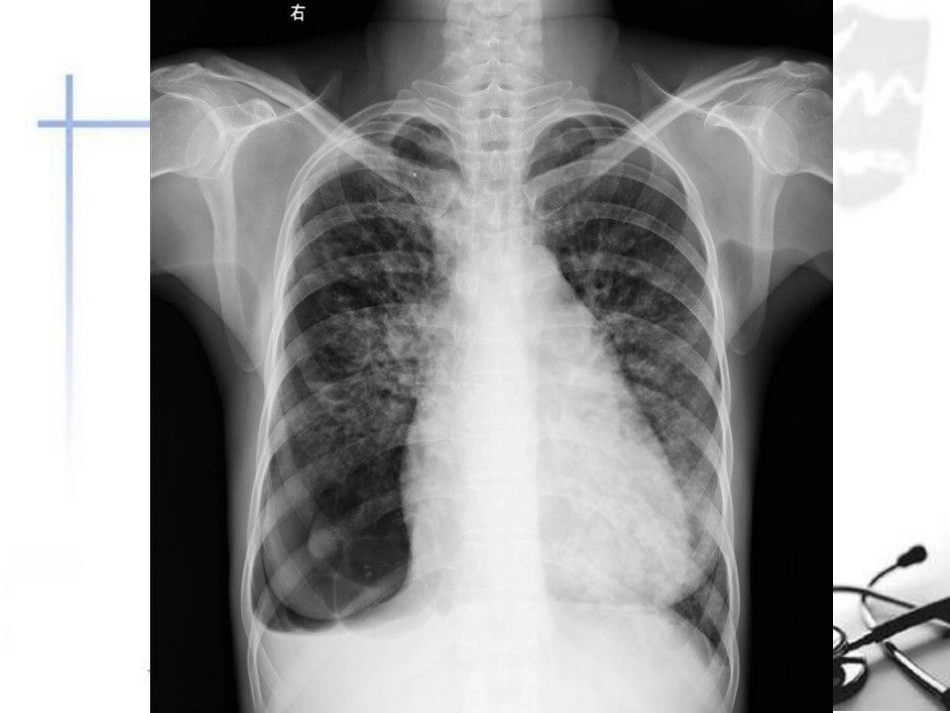

肺水肿的X线表现老A影像园志愿者Case•女性、46岁•胸闷、心慌、气促月余、咳嗽、少痰•查体:体温37.8,双肺呼吸音粗,可闻及干湿性罗音诊断结果•风湿性心脏病(二尖瓣狭窄)•肺淤血伴右下肺大泡肺纹理增多增粗边缘模糊片状模糊影肺大泡主要内容•肺淤血的X线表现•间质性肺水肿的X线表现•肺泡性肺水肿的X线表现•复张性肺水肿的X线表现肺水肿发生机制•压力性肺水肿---跨血管壁有效滤过压增高引起•通透性肺水肿---肺毛细血管壁通透性增高•混合性肺水肿---高原性肺水肿、神经原性肺水肿EVLW={(SA×Lp)〔(Pmv-Ppmv)-σ(πmv-πpmv)〕}-Flymph•EVLW为肺血管外液体含量•SA为滤过面积•Lp为水流体静力传导率•Pmv和Ppmv分别为微血管内和微血管周围静水压•σ为蛋白反射系数•πmv和πpmv分别为微血管内和微血管周围胶体渗透压•Flymph为淋巴流量•SA×Lp=Kf肺毛细血管壁通透性•(Pmv-Ppmv)-σ(πmv-πpmv)•跨血管壁有效滤过压肺淤血VS肺水肿•肺静脉高压:肺毛细血管-肺静脉压超过1.33KPa(10mmHg)•肺淤血:轻者•间质性肺水肿:压力>3.33KPa(25mmHg)•肺泡性肺水肿(中央型):压力进一步升高,血浆外渗到肺泡肺淤血的X线表现•属肺多血,指肺静脉回流受阻,使血流滞留在肺静脉系统内,肺静脉扩张•肺野透明度降低,呈模糊条纹状影•以中、下肺野显著,有时呈网状或圆点状•肺门影增大间质性肺水肿X线表现•液体积聚在肺间质内•间隔线•肺血重新分布•支气管周围袖口症•肺纹理及肺门血管增粗、模糊•肺脏透亮度下降•胸膜增厚胸腔积液间隔线•Kerley’sABC线阴影•Kerley’sB线是最重要的X线征象---正位,肋膈角处胸膜下厚度为1-2mm,长约2cm,与胸膜垂直---侧位,与胸骨下及膈胸膜垂直的线形阴影•肺间质异常的其他疾病亦可见间隔线---肺间质纤维化、重金属盐沉着症和癌性淋巴管炎女,59高血压糖尿病肾病奇静脉扩张支气管周围套袖样改变Kerley’sABC•Kerley’sA线(箭头)不透明线,从外周至肺门,为外周和中心淋巴组织的交通支液体潴留所致•Kerley’sB线(白色箭头)短的水平线,位于肺基底部,与胸膜表面垂直,为肺叶间隔膜水肿所致•Kerley’sC线(黑色箭头)位于肺基底部的不透明网格状线肺血重新分布•正常立位胸片---上肺野的血管阴影比下肺野的细•左心功能不全肺淤血---上肺野的血管阴影增粗、增多,下肺野血管阴影变细,与正常比呈上下逆转现象•机制很复杂…支气管周围袖口症•正常时肺门区可见一个或两个支气管断面形成的环形阴影,一般为上叶前段支气管,也可为下叶背段或舌叶支气管。其厚度约为1mm左右,边界清楚•间质性肺水肿时,支气管周围结缔组织内有液体存积,支气管壁形成的环形阴影增厚,边缘模糊间质性肺水肿其它X线表现•肺纹理及肺门血管增粗、模糊•肺脏透亮度下降•胸膜增厚•胸腔积液---严重的肺水肿可引起少量胸腔积液---胸膜腔内的液体来自壁层胸膜肺泡性肺水肿•中央型肺水肿•弥漫性肺水肿•局限性肺水肿中央型肺水肿•呈“蝶翼状”分布•常见于心脏和尿毒症患者•治疗及时一般很快吸收消失•治疗不及时,肺泡内除渗液外,可凝固的纤维蛋白和巨噬细胞所填充•可产生炎性改变,肺水肿可继发感染蝶翼征•指位于两肺中内带的大片状阴影,肺野的外带、肺尖、肺脏基底部、叶间裂周围和大血管附近病变轻微或正常弥漫性肺水肿•全弥漫性分布于两肺野•大小和密度不等,轮廓不清•可融合呈斑片状阴影•以非心源性---成人急性呼吸窘迫综合征(ARDS)白肺ARDS局限性肺水肿•肺泡性肺水肿所产生的阴影•呈局限性,以右侧多见•与心脏病患者喜欢右侧卧位和心脏增大压迫左肺动脉,使左、右肺肺血液量不同所致肺泡性肺水肿X线•1.腺泡实变的结节影,0.5cm~1.0cm,边缘模糊,很快融合•2.小叶实变的斑片影,很快融合成大片•3.大片融合影,有含气支气管征•4.中央型两肺的中、内带,蝶翼征•5.弥漫性广泛分别在肺野中、内带•6.单侧、不对称与体位有关。体位与病变分布的关系受重力影响•7.阴影动态变化从下、内很快向上、外发展•8.1~2天可有很大变化•9.胸腔积液少量•10.多与间质性肺水肿并存•11.短期内阴影变化快复张性肺水肿•Reexpa...